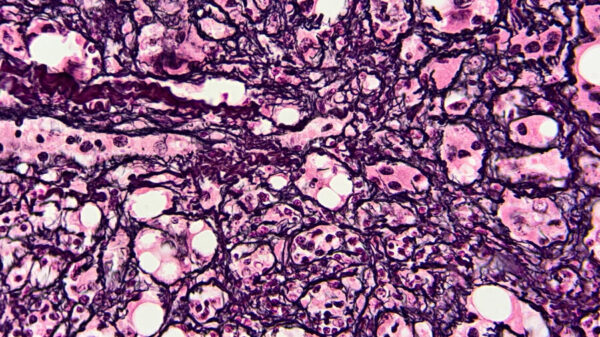

• Hematoxilina y eosina (H&E): Esta es una técnica histoquímica que utiliza la hematoxilina para teñir los núcleos celulares (unión específica al ADN) y la eosina para teñir el citoplasma (unión a proteínas ácidas). Proporciona información básica sobre la estructura celular y los tejidos.